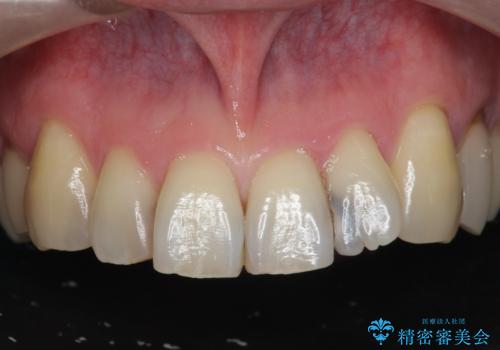

[ セラミック治療 ] 前歯の見た目を改善したい

![[ セラミック治療 ] 前歯の見た目を改善したいの症例 治療前](https://seimitsushinbi.jp/wp/wp-content/uploads/2025/10/IMG_9990-2-500x350.jpg?v=1761816440)

![[ セラミック治療 ] 前歯の見た目を改善したいの症例 治療後](https://seimitsushinbi.jp/wp/wp-content/uploads/2025/10/IMG_9934-500x350.jpg?v=1761816431)